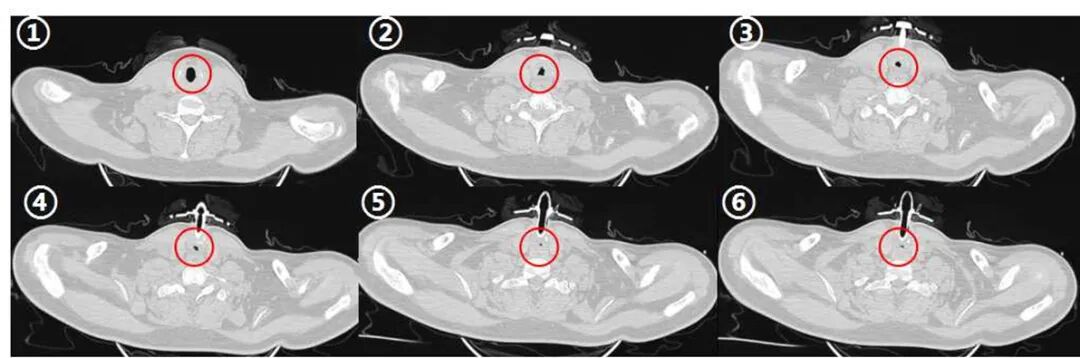

完成术前评估后,马上进行第一次气管镜,在方苏榕主任的指导下,呼吸介入医师常立功迅速完成气道评估,发现声门下2.5cm处气管闭塞,肉芽组织增生伴瘢痕形成,无法进镜,医生使用电圈套器和激光清理肉芽和瘢痕组织,后使用冷冻和球囊扩张再通狭窄气管,最后局部使用糖皮质激素抑制肉芽组织增生。

术后,小张感觉呼吸较前好转。为了达到更好的治疗效果,方苏榕和常立功医师一鼓作气连续完成3次气管狭窄再通术,小张终于可以简单发音。再次经过联合会诊和综合评估,在完成24小时的堵管后,成功拔除小张的气管切开套管。